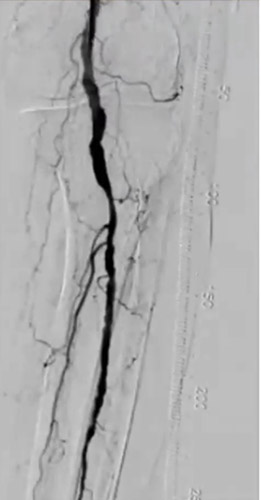

DAは閉塞していたが内腔はあるので穿刺を検討したが、難しいと判断しPTAを穿刺した。PTA経由でATAにレトログレードアプローチを行いDAからシースを挿入するため、1gワイヤーを進めたがATA(Anterior Tibial Artery)方向へワイヤリング出来ないため、Zizai™をPOP方向へ進め造影した(図3)。ATA入口部は狭窄しており、更に末梢は閉塞していることを確認した。ATA入口部へワイヤー通過に成功し急峻な角度ではあったがZizai™を追従させ(図4)、ATAは閉塞血管でありワイヤールートはSubでも良いと判断しワイヤーナックルにて末梢まで進めた。DAを18G針で穿刺をしワイヤーランデブーに成功した(図5)。その後、DAに4Frシースを挿入し、2.5㎜径バルーンでATAを拡張したあと、PTAのワイヤーとZizai™を抜去後にアプローチサイトの止血を行い、ATAの4Frシースからガイディングシースへ入れ替えを行った。